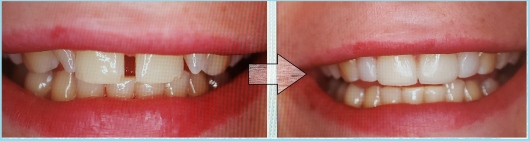

- Braki zębowe

Jestem Amerykaninem, ale mieszkam w Polsce ponad 10 lat. Zajmuję się zachowawczą, leczeniem kanałowym pierwotnym i wtórnym pod mikroskopem, protetyką i prostą chirurgią. Wykonuję też Bonding i Flow Injection Technique.